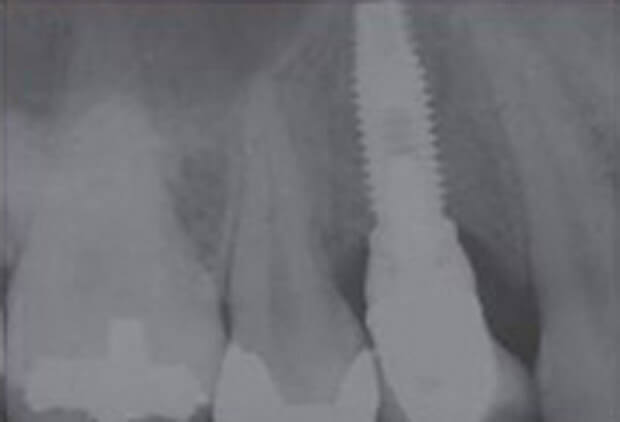

施術事例| インプラント治療 | 1歯/396,000円 |